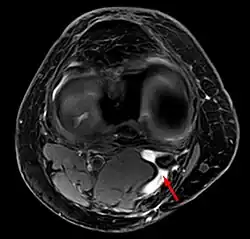

Un quiste de Baker en el espacio poplíteo -

quiste de Baker en MRI axial con comunicación entre el músculo semimenbranoso y el the músculo gastrocnemius.